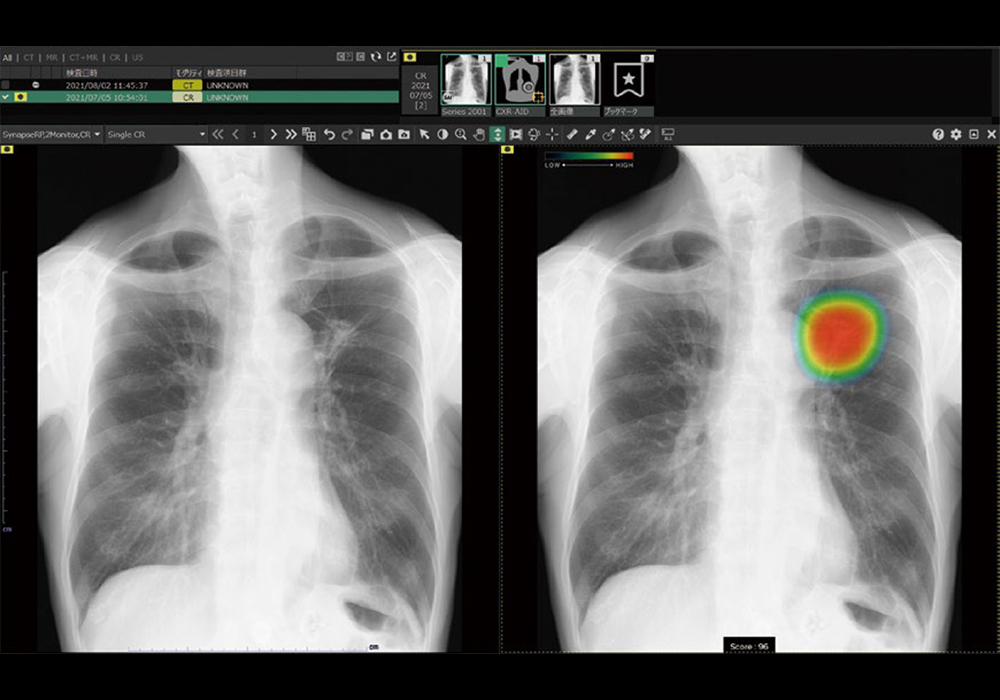

胸部X線画像診断システム(EX-Mobile)

AI技術を活用して、胸部レントゲン画像から肺がん・肺炎・気胸が疑われる箇所を検出し、医師の画像診断を支援するシステムです。